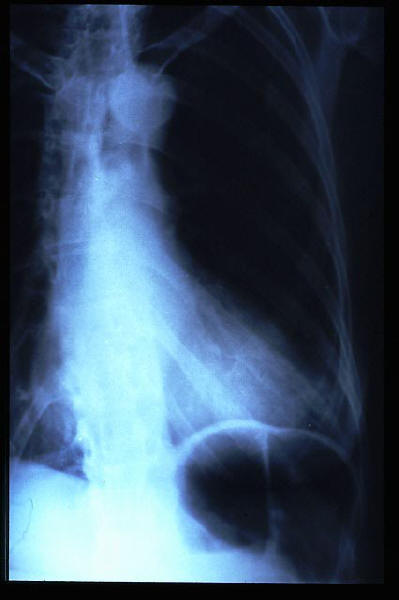

Hernia de hiato gigante.